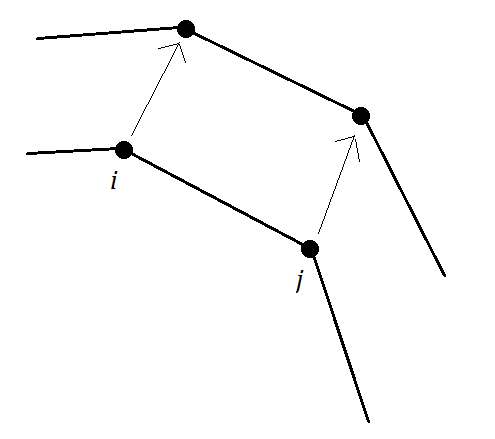

The Neumann boundary condition can be achieved in the same manner. Now it is the time to determine the boundary conditions for solving the governing equations. Fig. 2 displays two adjacent contour points, and , with their corresponding points after the displacement. The displacement vectors for these two points are:

| (10) |

Here we only consider the displacements in and directions, so . Therefore for boundary conditions of the boundary line consisting and contour points:

| (11) |

Boundary conditions for other boundary lines consisting of any two adjacent contour points will be computed in the same manner. After determining the boundary conditions, and producing triangular meshes, the problem is ready to be solved by Finite Element Method (FEM). In FEM first the domain is divided into simple geometrical shapes, like triangles, and then based on the assumption that the solution in the domain of each division, or element, has a simple form, the whole domain’s solution is computed. Polynomial approximation functions are useful choices for approximation of the solution in each element. The evaluation of these functions is simple they produce good approximates on small elements. It should be mentioned that in FEM one of the basic assumptions is that the solution in the domain is continuous. Therefore, it is necessary to have identical results on the shared sides of elements.